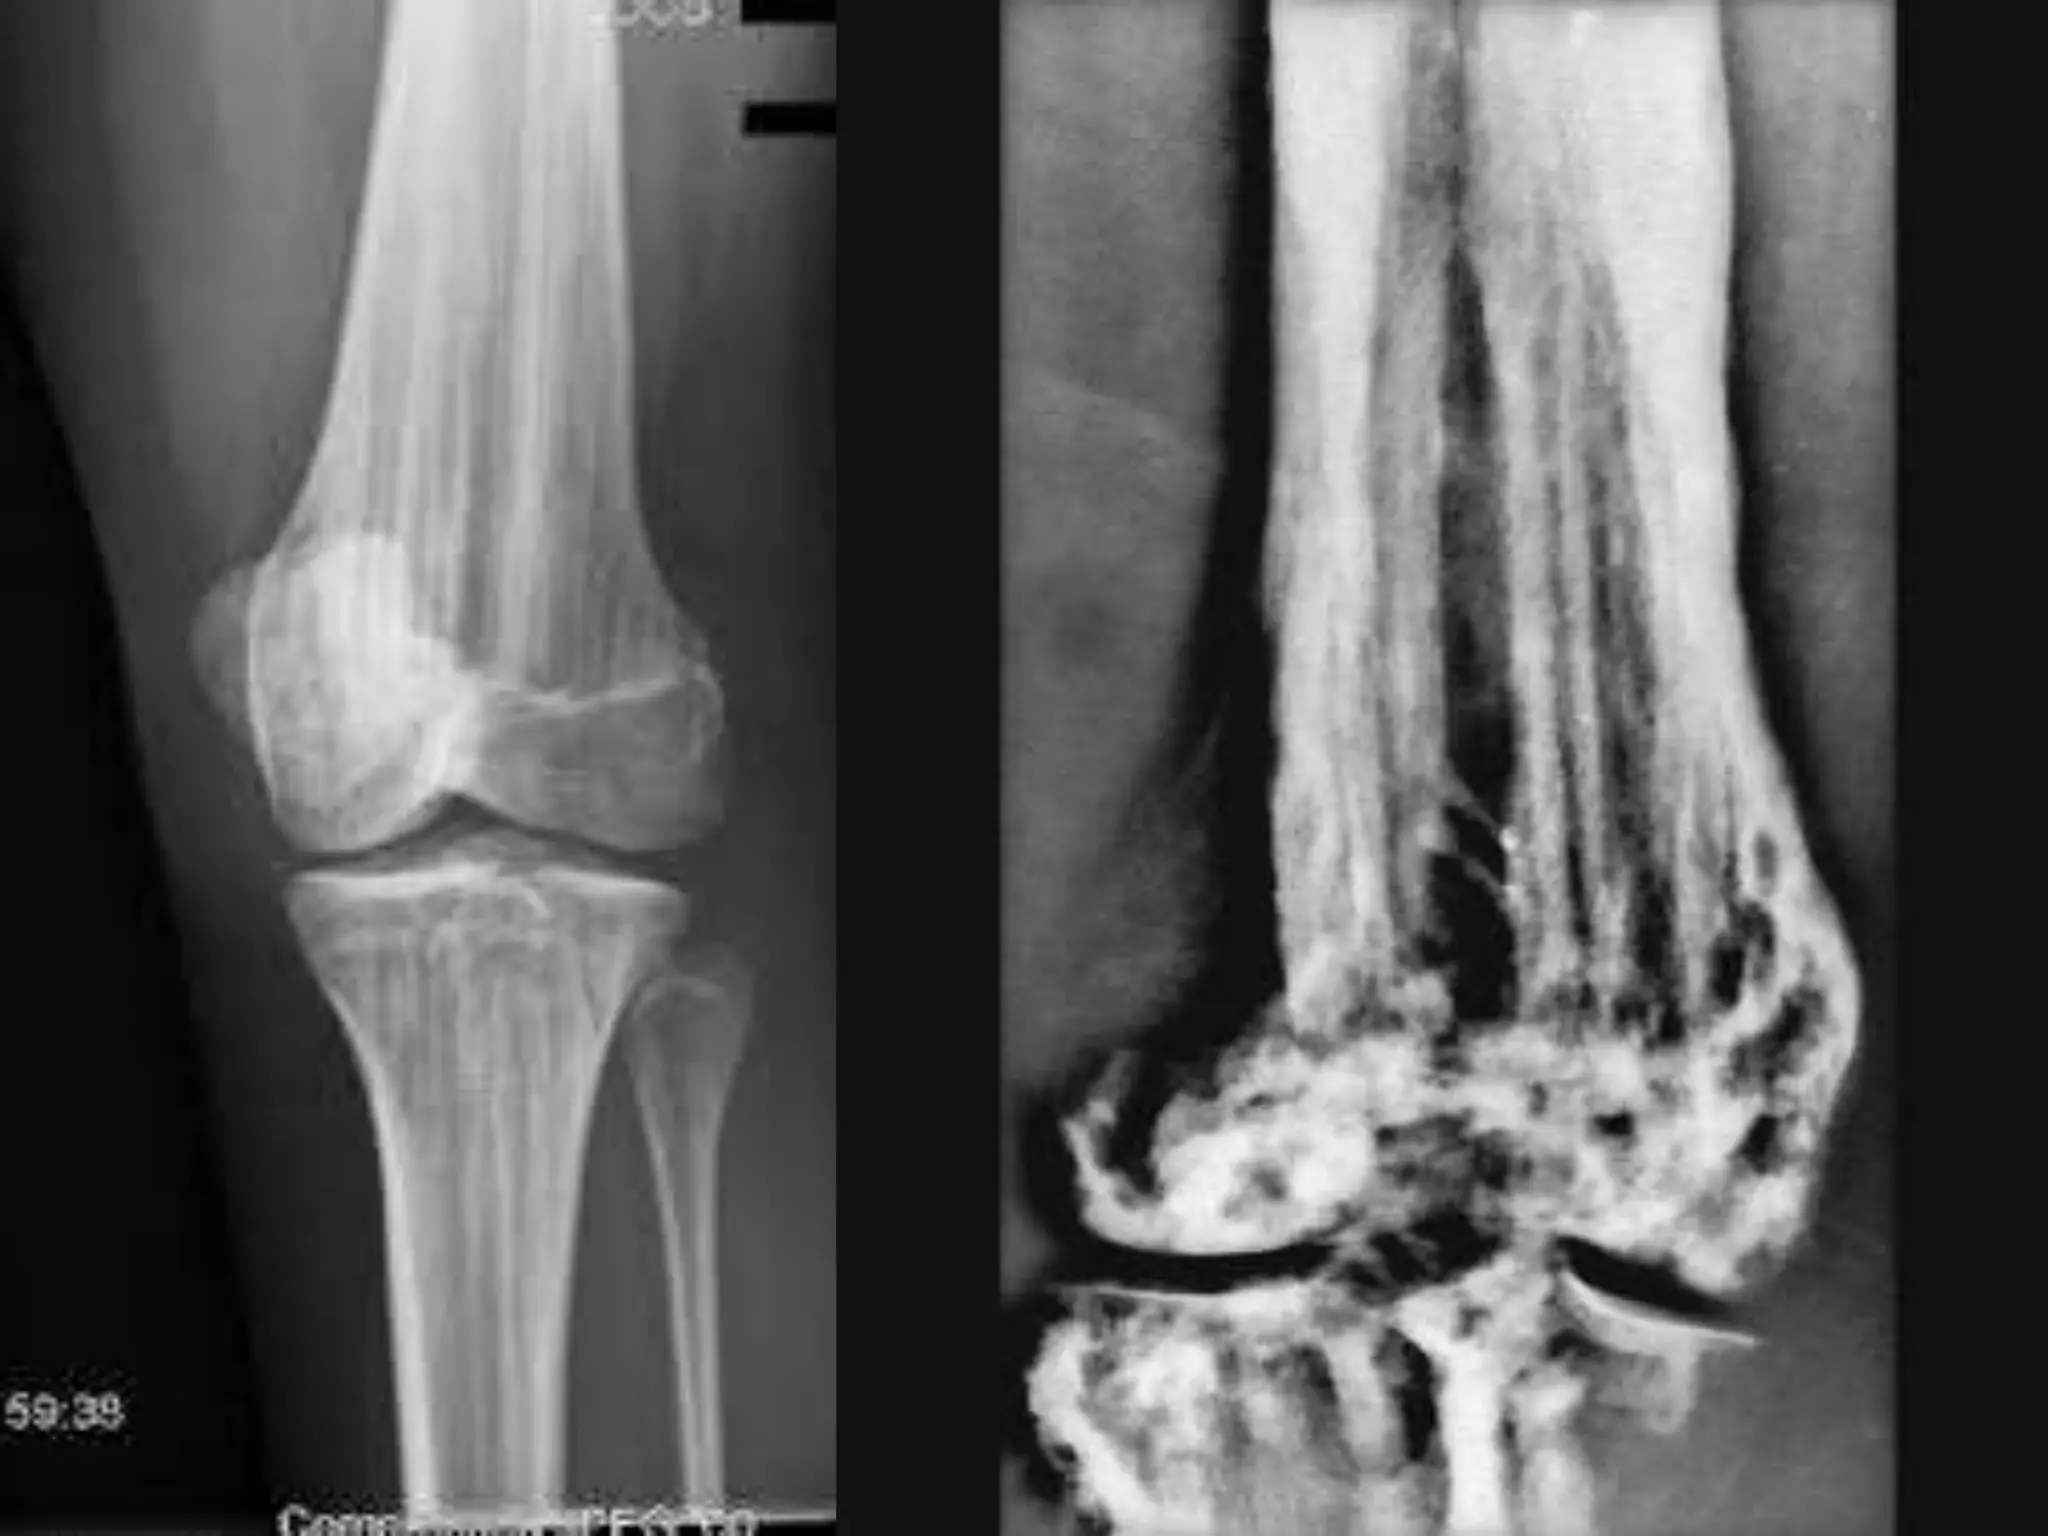

METAPHYSEAL DYSPLASIA (PYLE’S DISEASE) Autosomal Recessive. significantfeature is genu valgum. X-ray : bottle shaped distal femur/proximal tibia (Erlenmeyer Flask Deformity)

• 53.

Erlenmeyer flask “Bottleshape” distal femur/proximal tibia